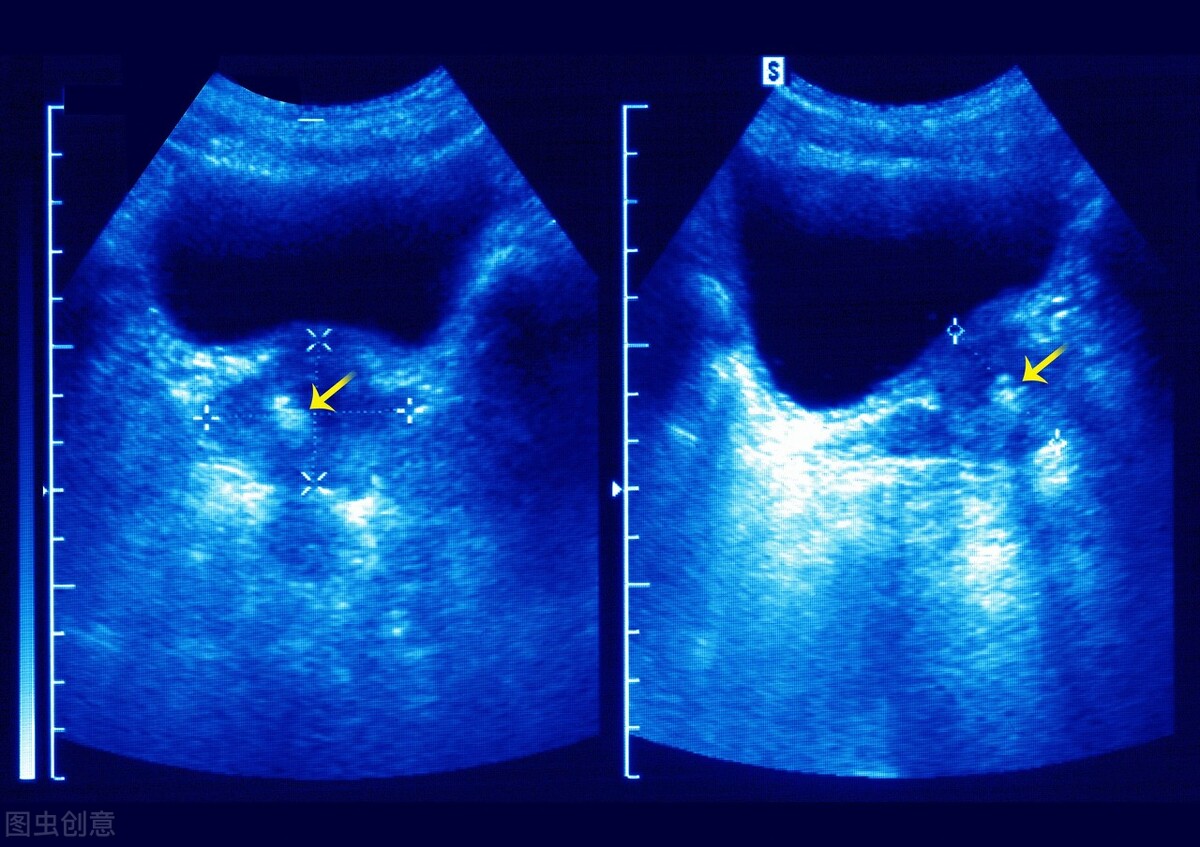

7、肝肾囊肿

很多人在进行B超检查时,都会发现肝脏或者肾脏中有囊肿。很多不明白的人,以为囊肿和癌症是一个意思,或者是认为囊肿能够演变为癌症,很是害怕。其实囊肿多数是因为先天性、炎症性或者创伤性而导致的,多数的囊肿直径较小,人体没有任何感觉,也无需治疗。不放心的可以定期进行影像学检查即可。

如果囊肿直径较大且出现压迫症状,那么是需要手术治疗的。